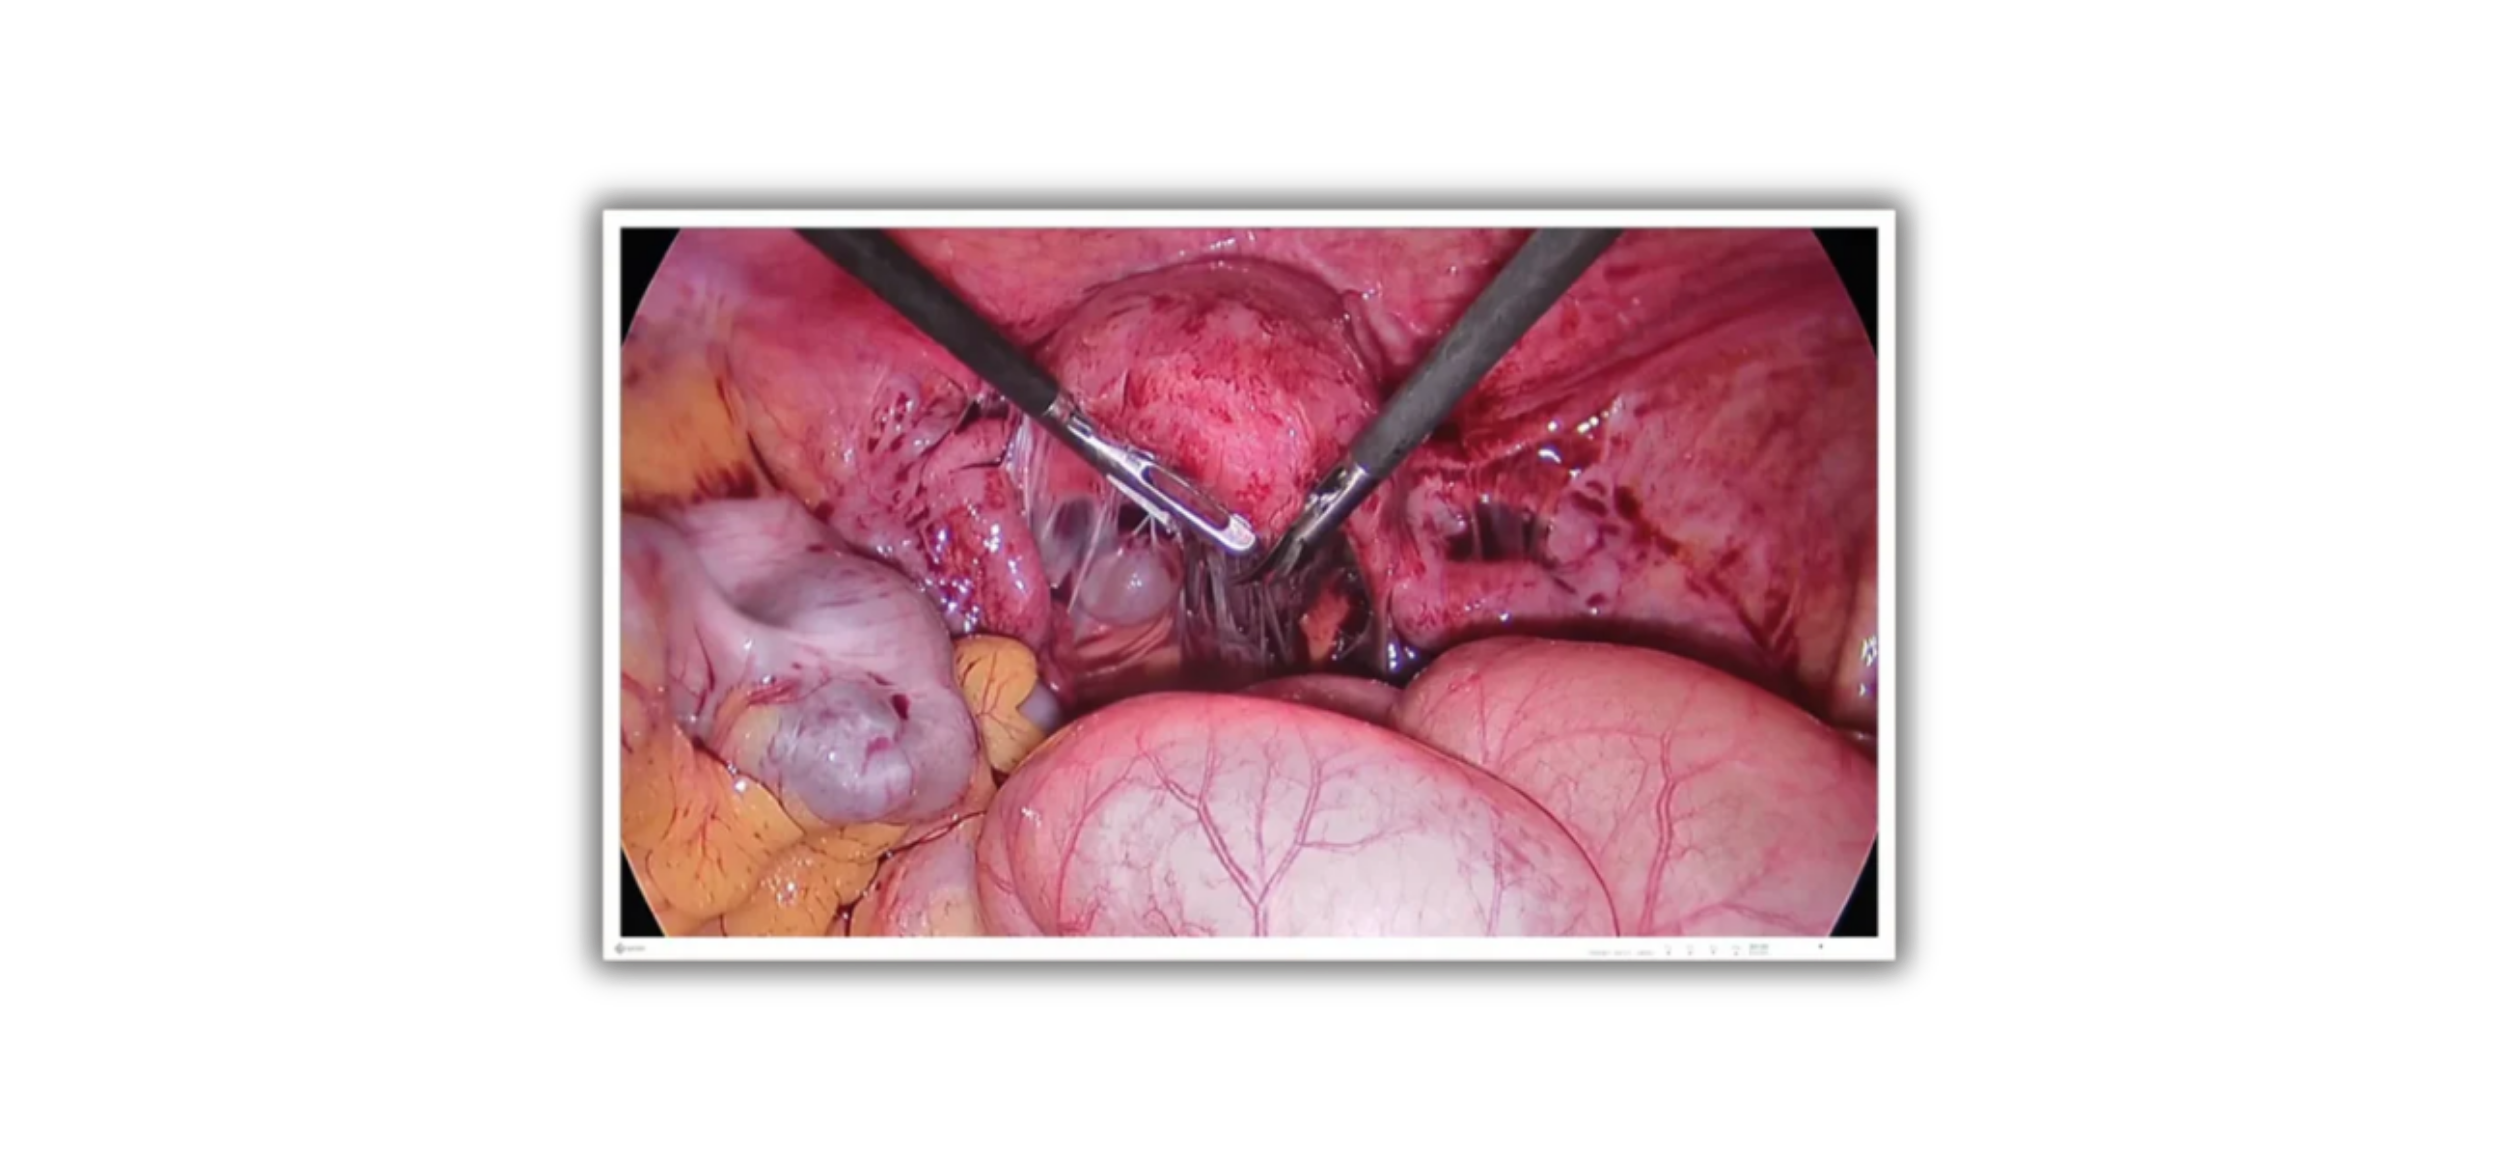

Médical

- Solutions d'affichage à la pointe

- Salles d'opération, radiologie

- Interventionnelle